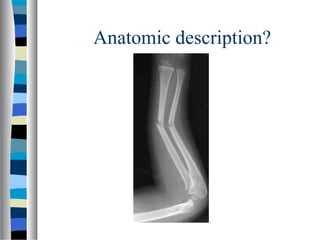

Anatomic description?

Anatomic description

 Simple, transverse,

non-communited

midshaft radial and

ulnar fracture with

30 degrees apex

radial angulation.